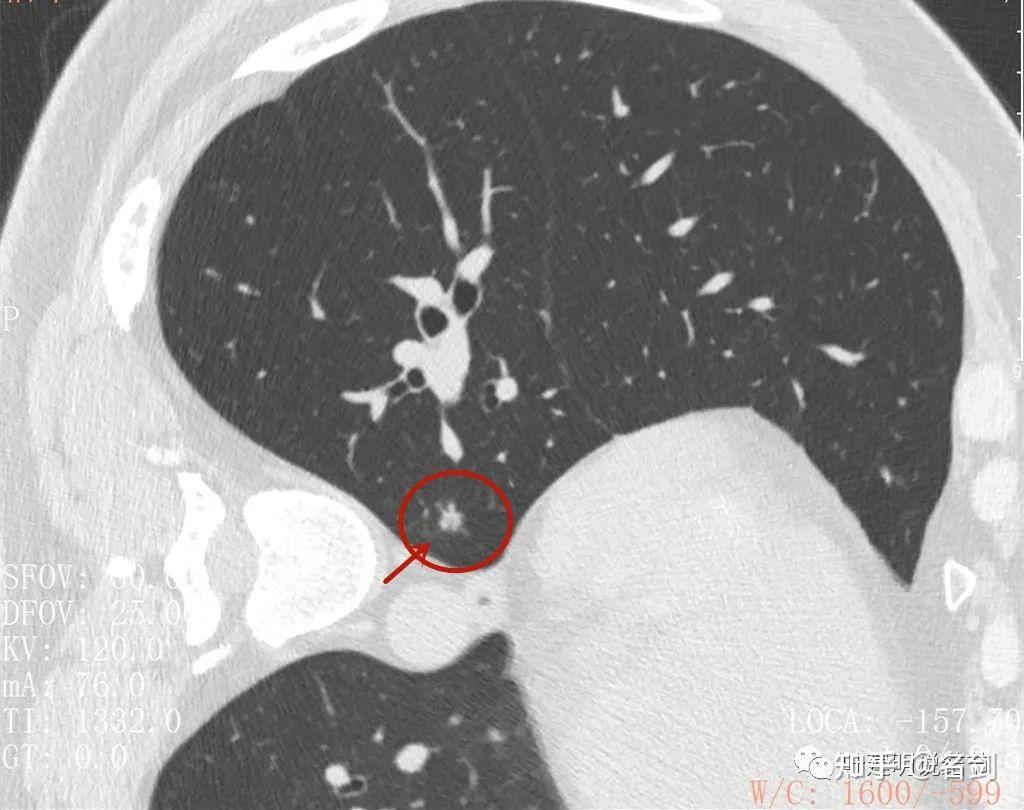

47岁,胸部亚实性结节,请各路高手会诊,下周手术-_病理已出

形态很典型的10mm实性结节,确诊却花了一个月!

细致剖析肺结节到底是不是癌?郑州30岁小伙来金华面诊